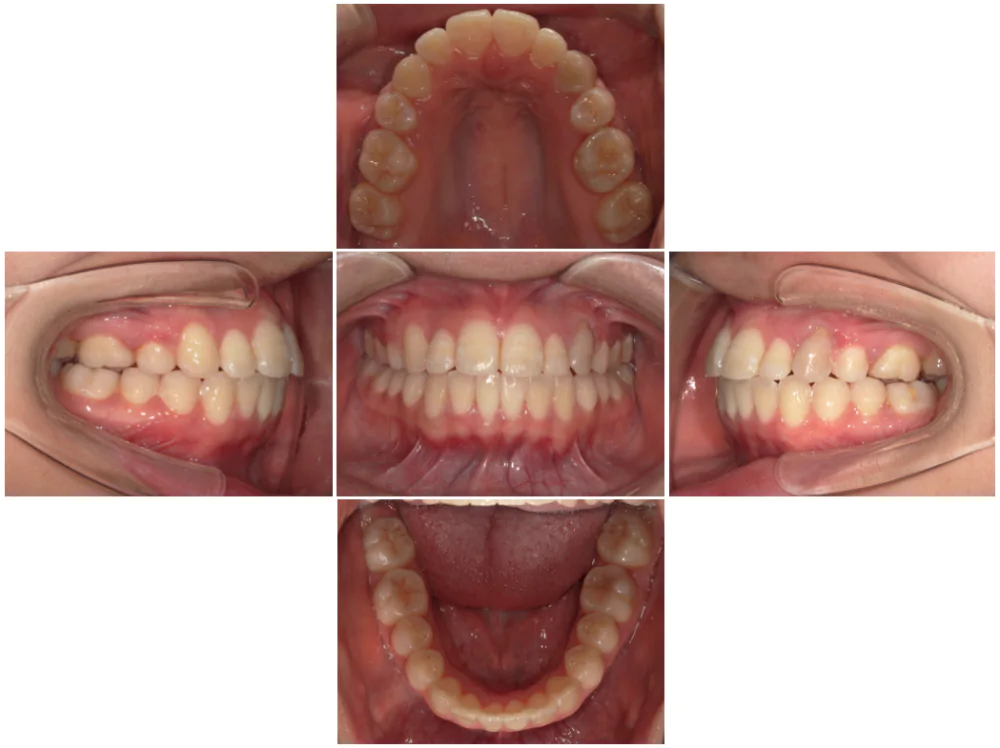

症例2

| 来院時の主訴 | 前歯がガタガタ |

| 医院での対応や適用装置 | マウスピース矯正装置を使用して主訴である叢生の改善を行ないま |

| 通院期間 | 1年3ヶ月 |

| 通院回数 | 9回 |

| 治療費用総額 | 819,500円(税込) |

| リスクと副作用 | 矯正治療による歯の移動に伴う痛み、歯根吸収、虫歯 |